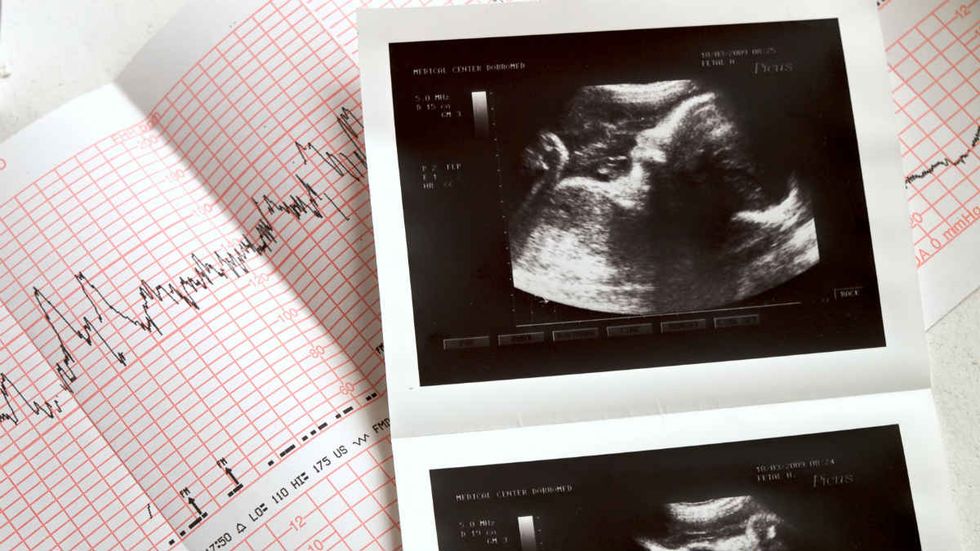

The Supreme Court has opted to leave in place a pro-life Kentucky law that requires women seeking abortion to see an ultrasound of their unborn children before making the decision to abort.

In a lengthy list of court orders put out Monday morning, the Supreme Court declined to take up the case of EMW Women's Surgical Center v. Meier — a challenge to a Kentucky law that requires women seeking abortion to be shown an ultrasound of their unborn children before making a final decision.

Earlier this year, the law was upheld by a ruling of the Sixth Circuit Court of Appeals. Opponents of the law — such as the ACLU of Kentucky — argue that by compelling abortionists to show women ultrasounds of their children, the law violates the free speech rights of abortion providers. The appeals court, however, found the statute's ultrasound requirements to be within the parameters of the First Amendment as it applies to speech required in professional settings.

"We hold that [the law] provides relevant information," the Sixth Circuit opinion reads. "The information conveyed by an ultrasound image, its description, and the audible beating fetal heart gives a patient greater knowledge of the unborn life inside her. This also inherently provides the patient with more knowledge about the effect of an abortion procedure: it shows her what, or whom, she is consenting to terminate. That this information might persuade a woman to change her mind does not render it suspect under the First Amendment. It just means that it is pertinent to her decision-making."